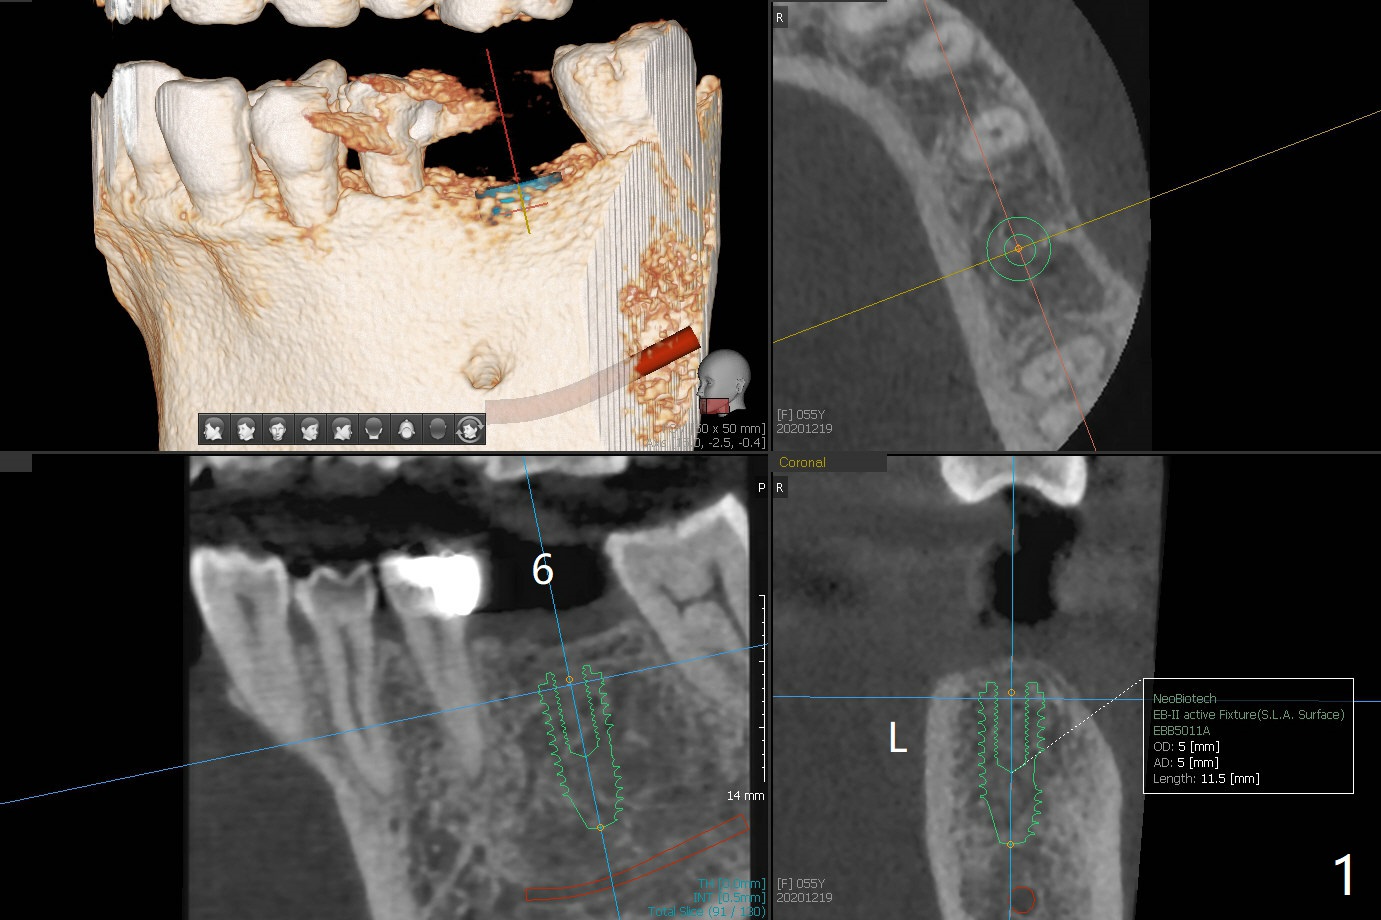

55岁女失去左下6十八年,害怕治疗,但是害怕面部变形才下决心种植,牙槽嵴宽(图一),骨质密度偏高(图二)。完成5x10毫米钻洞,植入4.5x10毫米报废植体,判断张口度。如果病人张口有余地,加深钻洞